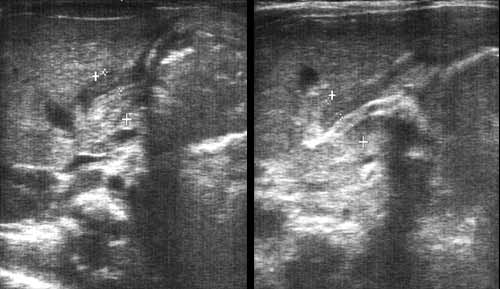

Врожденный пилоростеноз.

Рис. 4. Больной В., 1 мес. Врожденный пилоростеноз.